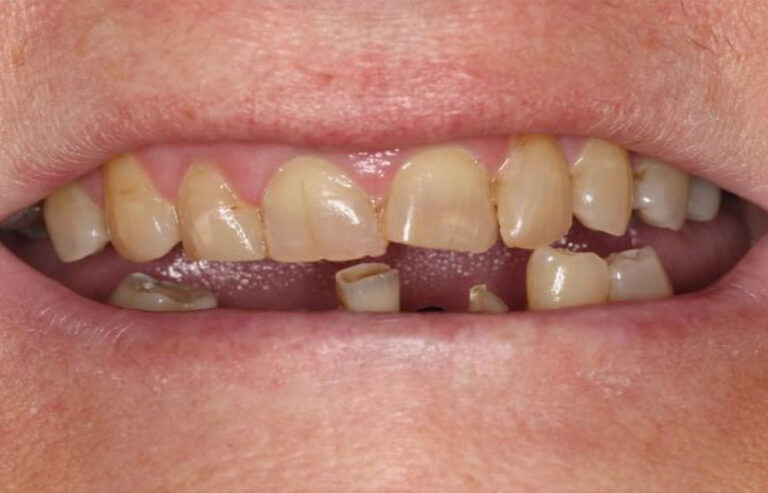

Consultation & 3D Scan

We begin with a comprehensive clinical evaluation and advanced 3D imaging to assess bone quality, anatomy, and functional needs. This allows us to design a fully customized treatment plan from day one.